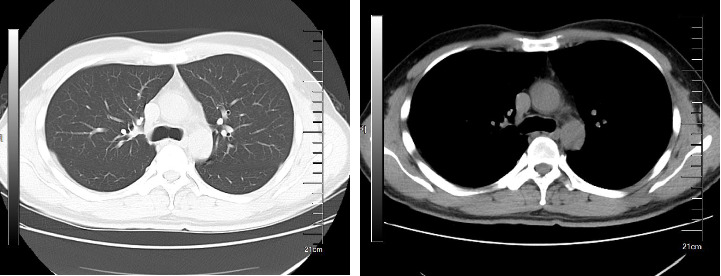

COVID-19急性后后遗症心血管综合征(PASC-CVS)是指在感染COVID-19后4周或更长时间出现的广谱心血管症状,通过标准检查无法诊断为心血管疾病。常见症状包括运动不耐受和心动过速,以及胸痛、胸闷和呼吸困难等持续性问题。PASC-CVS显著影响患者生活质量;然而,目前缺乏有效的治疗方法。本文报告两例PASC-CVS患者在服用肃消九心丸后,心血管症状得到良好控制。我们的研究结果可能为PASC-CVS的临床治疗提供一种新的方法。

Postacute Sequelae of COVID-19 Cardiovascular Syndrome (PASC-CVS) refers to a broad spectrum of cardiovascular symptoms that manifest four weeks or more after infection with COVID-19, which cannot be diagnosed as cardiovascular disease through standard examinations. Common symptoms include exercise intolerance and tachycardia, alongside persistent issues such as chest pain, chest tightness, and difficulty breathing. PASC-CVS significantly affects patients' quality of life; however, effective treatments for this condition are currently lacking. In this report, we present two cases of PASC-CVS patients who experienced well-controlled cardiovascular symptoms following treatment with Suxiao Jiuxin Pills. Our findings may offer a novel approach to the clinical management of PASC-CVS.